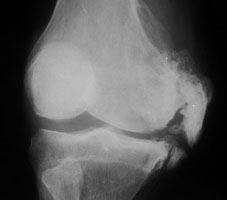

This eponym refers to avulsion of the medial femoral condyle at the origin of the medial collateral ligament. With Pelligrini-Stieda disease, chronic trauma (and tears) to the medial collateral ligament produces ossification.

- Click on the image for a larger versionAOblique radiograph of the knee. The typical appearance of severe Pelligrini-Stieda disease.